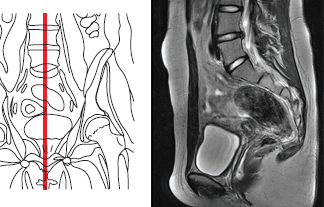

Магнитно-резонансная томография (МРТ) органов малого таза проводятся после предварительного ультразвукового обследования этого анатомического региона.

- высокая разрешающая способность — на магнитно-резонансной томографии (МРТ) органов малого таза можно увидеть объекты размером до нескольких миллиметров и есть возможность получать изображение в любой плоскости;

Желательно проводить исследования органов малого таза на магнитно-резонансном томографе (МРТ) с напряженностью магнитного поля от 1,5 Тесла. В некоторых случаях Вам могут предложить введение внутривенное контрастного вещества для оценки характера процесса и его распространенности.

Магнитно-резонансное исследование (МРТ) органов малого таза 3,0 Т (тесла) не требует специальной подготовки больного, однако как мужчинам, так и женщинам желательно некоторое (не тугое) заполнение мочевого пузыря, то есть перед исследованием не рекомендуется опорожнять мочевой пузырь.